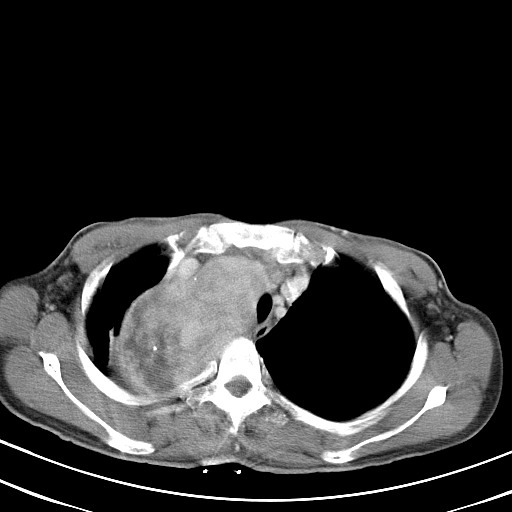

以下是引用汪涛同志在2007-8-2 0:40:00的发言:[br]病变虽然广泛,同时侵及双侧纵隔,但是无论左侧和右侧上下观察都是与右侧颈部甲状腺相延续的,而且强化幅度基本一致,又同时具有恶性病变病变的某些特征:肿块过大且密度不均,部分层面与正常纵隔结构分界不清,结合病史已有两年,考虑:胸内甲状腺肿恶变可能。[br]